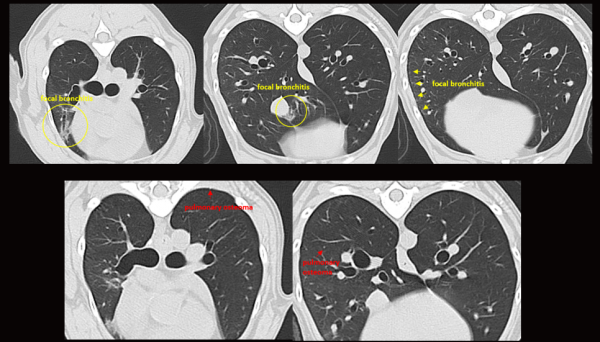

수술 후 별이는 복부 초음파, 그리고 두부 및 흉부 CT 촬영을 통해

종양의 전이 여부를 정밀하게 확인하였습니다.

다행히도 검사 결과, 다른 장기로의 전이는 발견되지 않았습니다.

수술 후 재진 사진에서는 종괴가 깨끗하게 제거되어 있고,

붉게 부풀어 있었던 결막도 정상적인 색과 모양을

되찾은 모습을 확인할 수 있습니다.